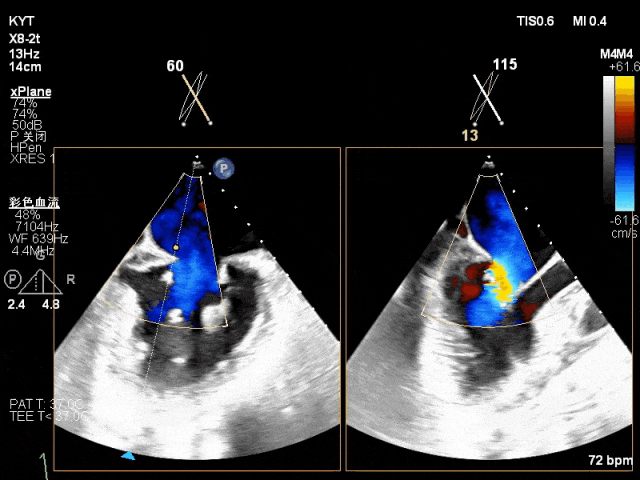

术前超声评估结果:

二尖瓣PC区收缩期脱向左房侧,其上可见飘带样回声。二尖瓣口左房侧见大量反流信号,主要呈偏心性并沿前叶走行达房顶并折返。

术前TTE及TEE影像:

TEE X-plane with color Doppler